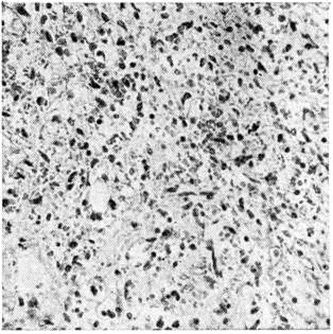

В костном мозге, по данным трепанобиопсии, на первых стадиях заболевания скопления бластных клеток являются очаговыми, в достаточном количестве обнаруживаются элементы деятельного костного мозга. Нередко наблюдаются острые расстройства кровообращения, участки гипоплазии, могут обнаруживаться некрозы. Прогрессирование заболевания характеризуется увеличением числа и размеров лейкозных разрастаний, их слиянием, а затем диффузной инфильтрацией ткани костного мозга. Количество нормальных кроветворных клеток заметно уменьшается. Часто имеется инфильтрация надкостницы, возможно распространение процесса в окружающие мягкие ткани. Развитие лейкозных разрастаний сопровождается выраженным рассасыванием костной ткани, преимущественно по типу гладкой резорбции. Очень редко в этом процессе принимают участие остеокласты. Вследствие частичного, а местами и полного рассасывания костных балок происходит значительное расширение костномозговых полостей, истончение, а в некоторых участках разрушение кортикального слоя. В раннем детском возрасте резкие изменения наблюдаются в зоне энхондрального окостенения. При острых Лейкозы редко отмечается очаговое новообразование атипичной костной ткани, богатой остеоидом, разрастание фиброзной ткани. Наряду с мелкими фокусами некроза иногда возникают обширные инфарктообразные коагуляционные некрозы, определяемые макроскопически в виде жёлто-белых сухих участков; в окружности наблюдаются кровоизлияния, возможно скопление макрофагов (рисунок 1). В области лейкозных разрастаний нередко обнаруживается истончение и частичный распад ретикулярных волокон. Описаны наблюдения с очаговым или диффузным миелофиброзом, который чаще выявляется при миелобластном Лейкозы. В таких случаях при пункции обычно не удаётся получить костный мозг и для установления диагноза необходимо исследование материала трепанобиопсии.